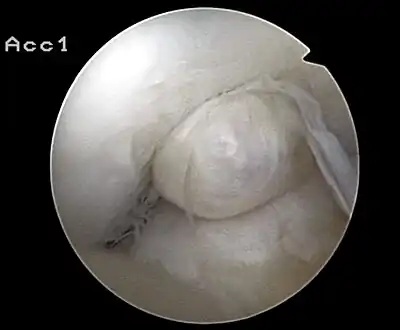

Arthroscopie diagnostique

La sécurité diagnostique la meilleure est obtenue par arthroscopie diagnostique. Ce procédé représente l'étalon-or pour le diagnostic de la rupture de LC. Ce procédé relève d'une chirurgie invasive au minimum, mais comporte certains risques, comme toute intervention chirurgicale dans le genou du patient[113]. Comme cependant le traitement chirurgical d'une rupture de LC sera conduit par chirurgie arthroscopique, il est possible d'enchaîner celle-ci immédiatement après l'arthroscopie diagnostique, par la résection partielle du ligament (pour une déchirure) ou la reconstruction en cas d'arrachement. Avec l'accroissement de la facilité de l'IRM, le nombre d'arthroscopies purement diagnostiques a nettement diminué ces dernières années[114],[115]. L'arthroscopie diagnostique est quand même utilisée comme précédemment comme procédé de choix pour une compréhension certaine du diagnostic de rupture de LC, en cas d'examen clinique confus et d'IRM difficile à interpréter[113].

Arthroscopie

L'opération proprement dite commence par l'introduction de l'arthroscope dans le genou du patient. Ceci permet de confirmer définitivement le diagnostic de rupture de LC. Les autres blessures, en particulier celles des ménisques, peuvent être soignées avant la reconstruction du LC.